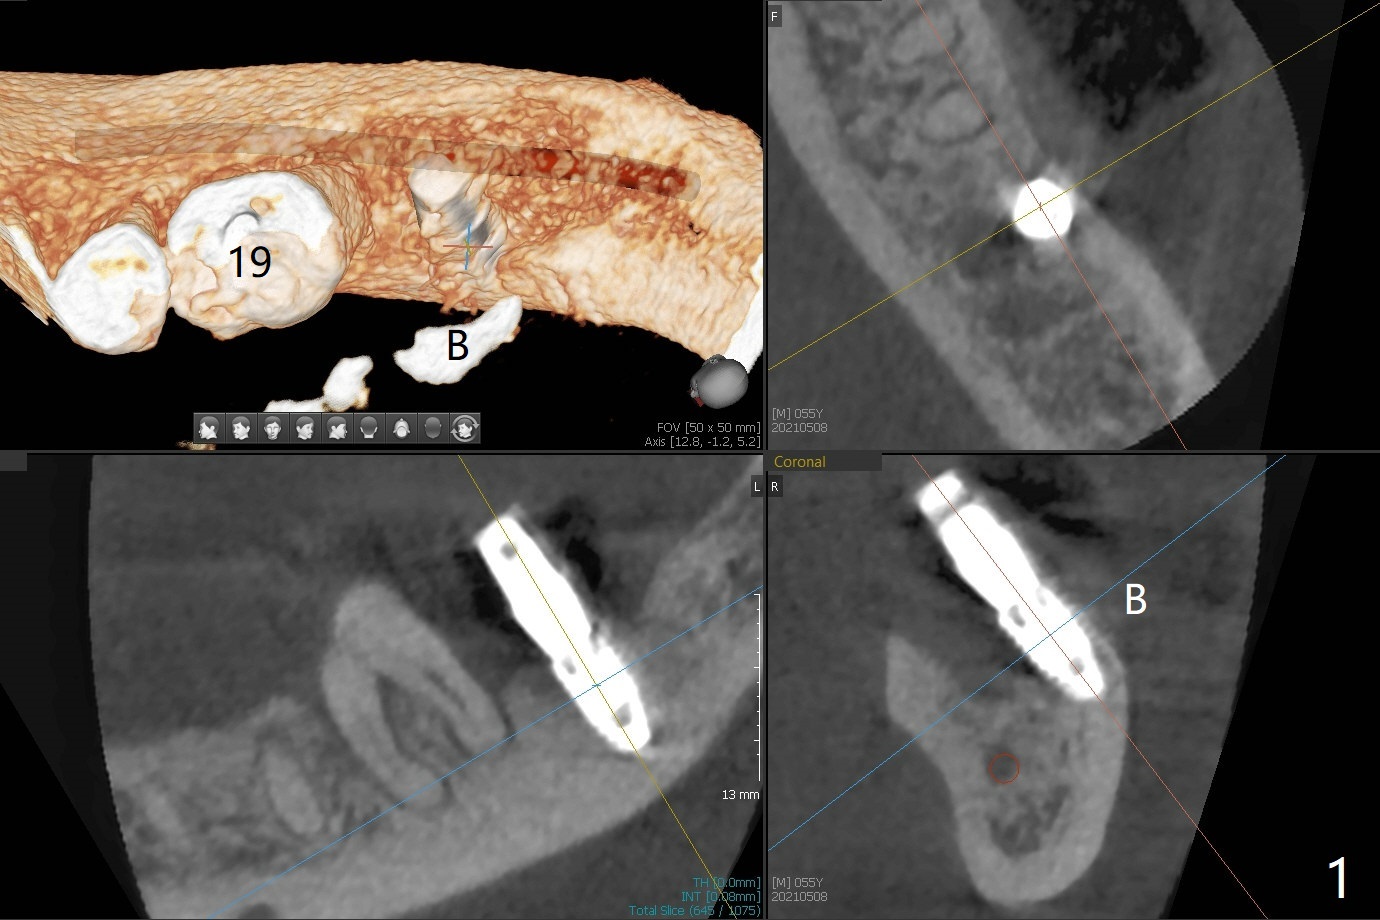

病人舌头大,取模时19号牙舌侧不全(图三),导板制作就没有覆盖舌侧(图四),导板向舌侧倾斜,不准确,植牙就太偏颊侧(图一)。取出植体还必须做近中颊侧切口,放置粘性骨粉和PRF膜(图二:*),PGA缝合,牙周胶水。